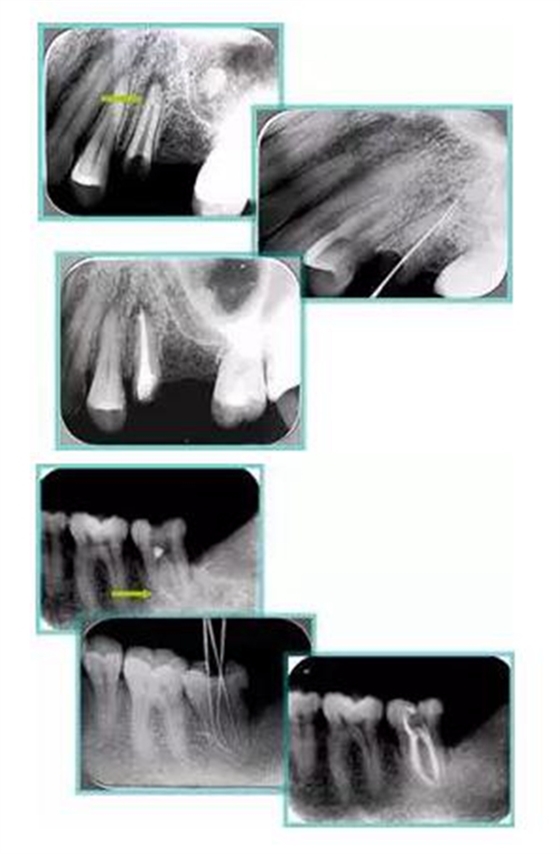

6. 鈣化

常見(jiàn)有修復(fù)性鈣化和增齡性鈣化。下面為根管鈣化 X 線(xiàn)片。

7. 器械折斷

下圖為器械折斷的 X 線(xiàn)片。箭頭處示折斷器械。

二、臺(tái)階

下圖箭頭處示臺(tái)階形成。